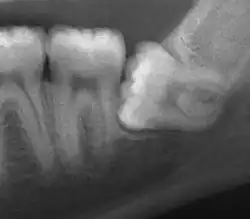

| Impacted wisdom tooth with a horizontal orientation | |